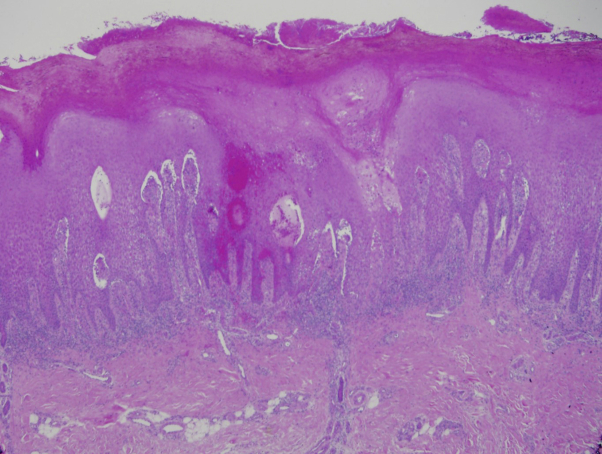

Fig 2.

Hematoxylin-eosin stain; original magnification, ×10. Biopsy of the left medial heel shows hyperkeratosis; an absent granular layer; a hemorrhagic thrombus with admixed neutrophils; acanthosis with elongated rete pegs; and dense, mixed inflammation in the papillary dermis.